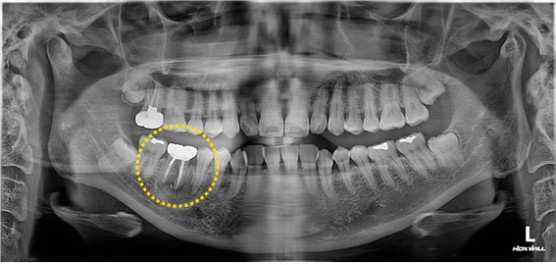

2024. 09. 30

이미지

1년 반 만에 환자분이 내원하셔서 사진을 찍게 되었습니다. 타치과에서 이런저런 이야기를 듣고 확인차 오신 거긴 한데, 제가 치료했던 치아 하방이 뼈로 잘 차있는 모습을 확인하게 되어 기분이 좋네요.

재신경치료가 실패할 수도 있지만, 이렇게 살릴 수만 있다면 그 어떤 임플란트보다도 가치 있는 치아가 될 것이라 생각됩니다. 오늘도 치아를 살리는 기쁨을 드리는 참조은치과였습니다.